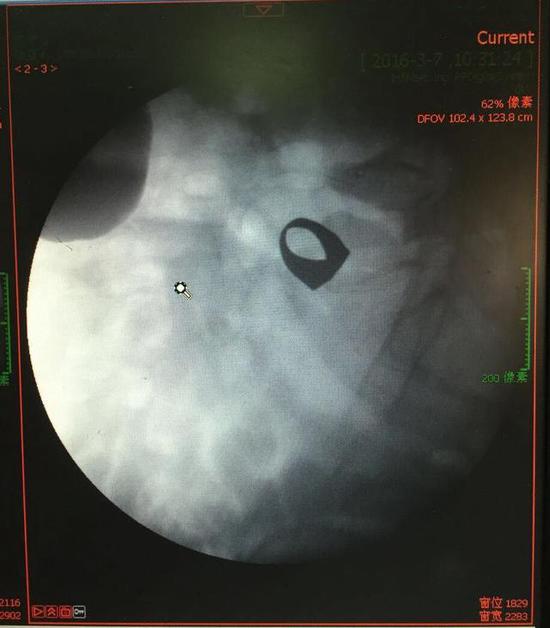

考慮到患者年齡較大,有冠心病,曾經中過風,高血壓極高危級,遂把老人安排在帶有監護的病房,立即給予吸氧,補液等治療。醫院立刻開啟綠色通道,醫護人員專門陪伴病人做了增強CT,腹部平片,和碘水造影,確定戒指的位置。檢查結果提示戒指位于右下腹小腸內,距回盲瓣體表投影約5cm。

3月9日,夏澤鋒教授細心的給病人做結腸鏡檢查,找到回盲瓣,調整結腸鏡鏡頭,快速的進入小腸。結腸鏡緩緩上行至距離回盲瓣5cm的小腸,沒有戒指。繼續上行,至20cm的地方,仍然沒有找到戒指。

此時一個又一個大大的疑問出現在每個在場的醫護人員腦海中,戒指還在小腸里嗎?戒指在哪個位置呢?夏教授立刻聯系放射科,拍片子,發現戒指已經移動了,從右側移動到了左側去了。放射科醫師建議,戒指有可能會繼續沿腸道下行,如果過了回盲瓣,就可以自行排出,免除手術痛苦。教授們采納了這個意見,立即給予促進胃腸道動力藥,枸櫞酸莫沙必利片,每日口服三次,另外配合灌腸治療,促進腸道蠕動,利于戒指排出。